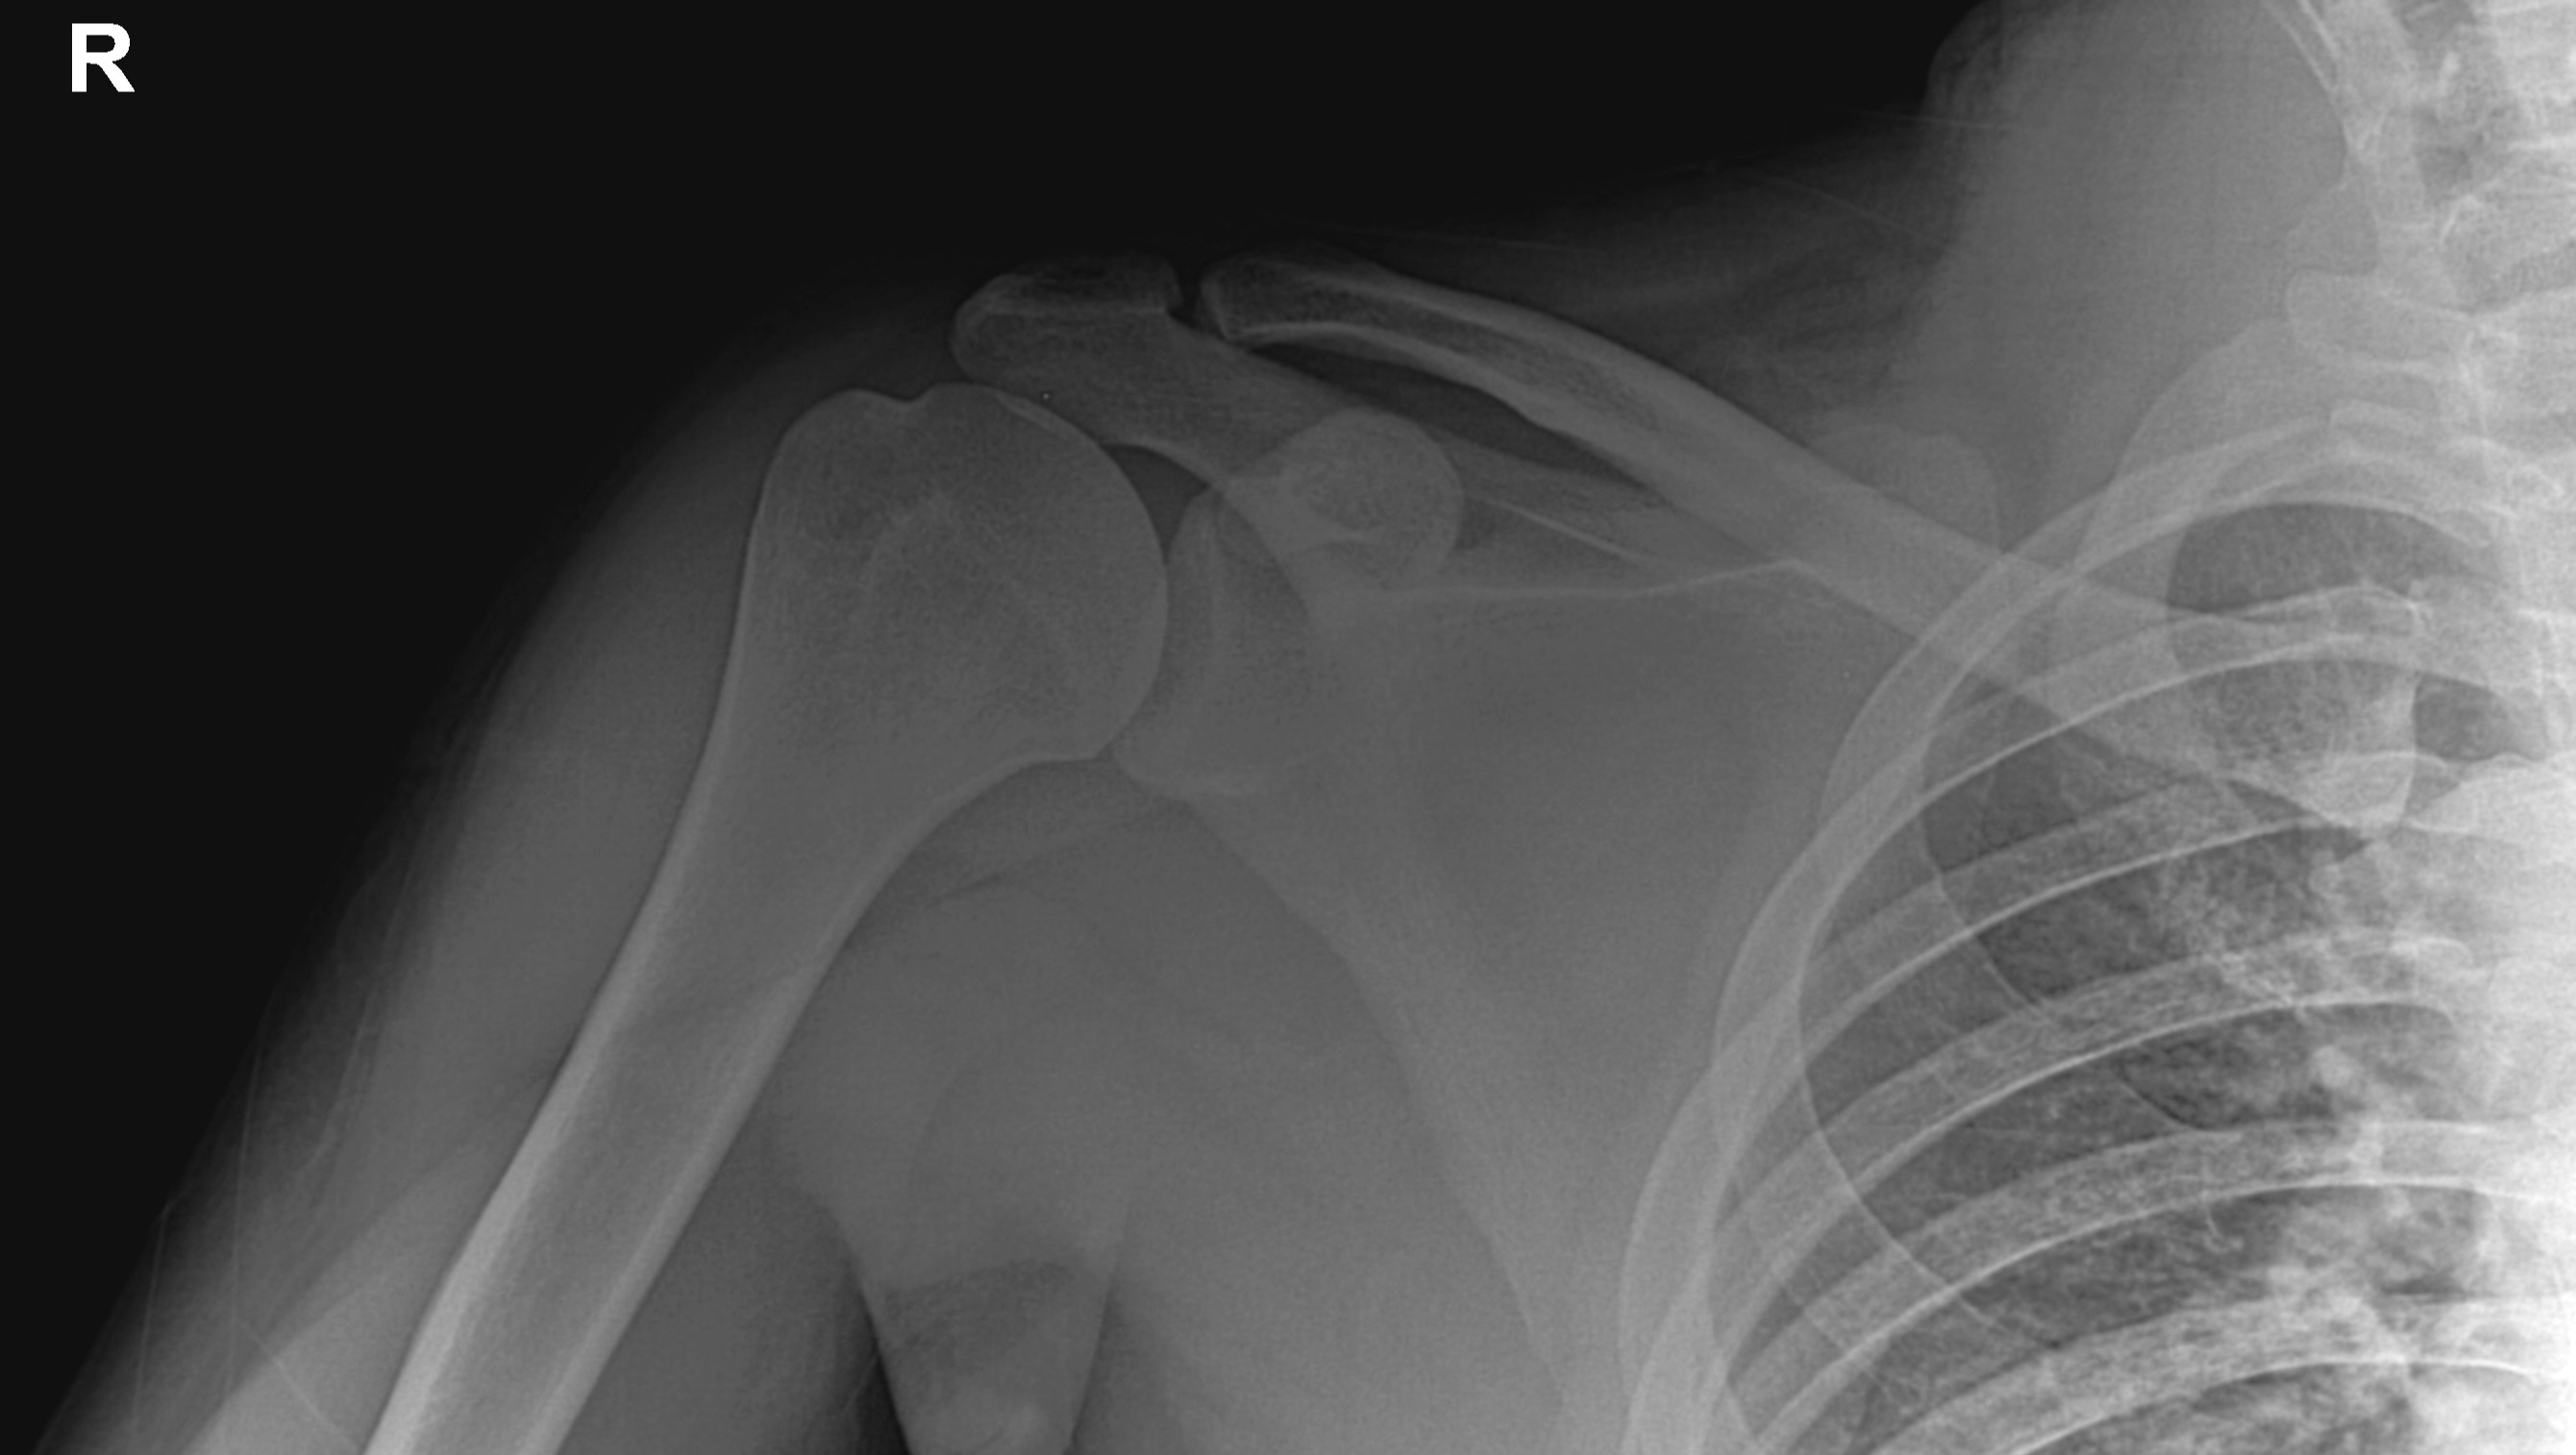

Tengo 24 años y siempre he sido una persona independiente y activa. Mi trabajo en tecnología y mi pasión por el deporte dependen totalmente de mi capacidad física. Sin embargo, hoy enfrento una situación que me ha obligado a detenerme: una rotura total de uno de los tendones principales de mi hombro, que ha comenzado a afectar seriamente la fuerza y estabilidad de mi brazo.

Lo que empezó como una lesión se ha vuelto algo mucho más serio. La lesión en mi hombro me ha provocado debilidad progresiva en mi brazo, episodios de hormigueo y temblores en mi mano, y un dolor constante en el hombro que se siente como una punzada profunda al intentar mover el brazo. Esto está afectando seriamente mi capacidad para trabajar y realizar actividades cotidianas. Ver cómo pierdo poco a poco la fuerza en mi herramienta de trabajo ha sido un golpe muy duro. Los médicos me han explicado que el tiempo es nuestro mayor enemigo; si no me opero pronto, la recuperación podría volverse mucho más difícil y podría perder la posibilidad de recuperar el movimiento normal de mi brazo.

I am 24 years old, and I have always been an independent and active person. My work in technology and my passion for sports depend entirely on my physical capabilities. However, today I face a situation that has forced me to stop: a full tear of one of the main tendons in my shoulder, which has begun to seriously affect the strength and stability of my arm.

What started as an injury has become something much more serious. The damage to my shoulder has caused progressive weakness in my arm, episodes of tingling and tremors in my hand, and constant shoulder pain that feels like a deep stab whenever I try to move. This is seriously affecting my ability to work and perform daily activities. Watching myself slowly lose strength in my primary 'work tool' has been a devastating blow. Doctors have explained that time is our greatest enemy; if I don't have surgery soon, recovery could become much more difficult, and I could lose the chance to regain normal movement in my arm.